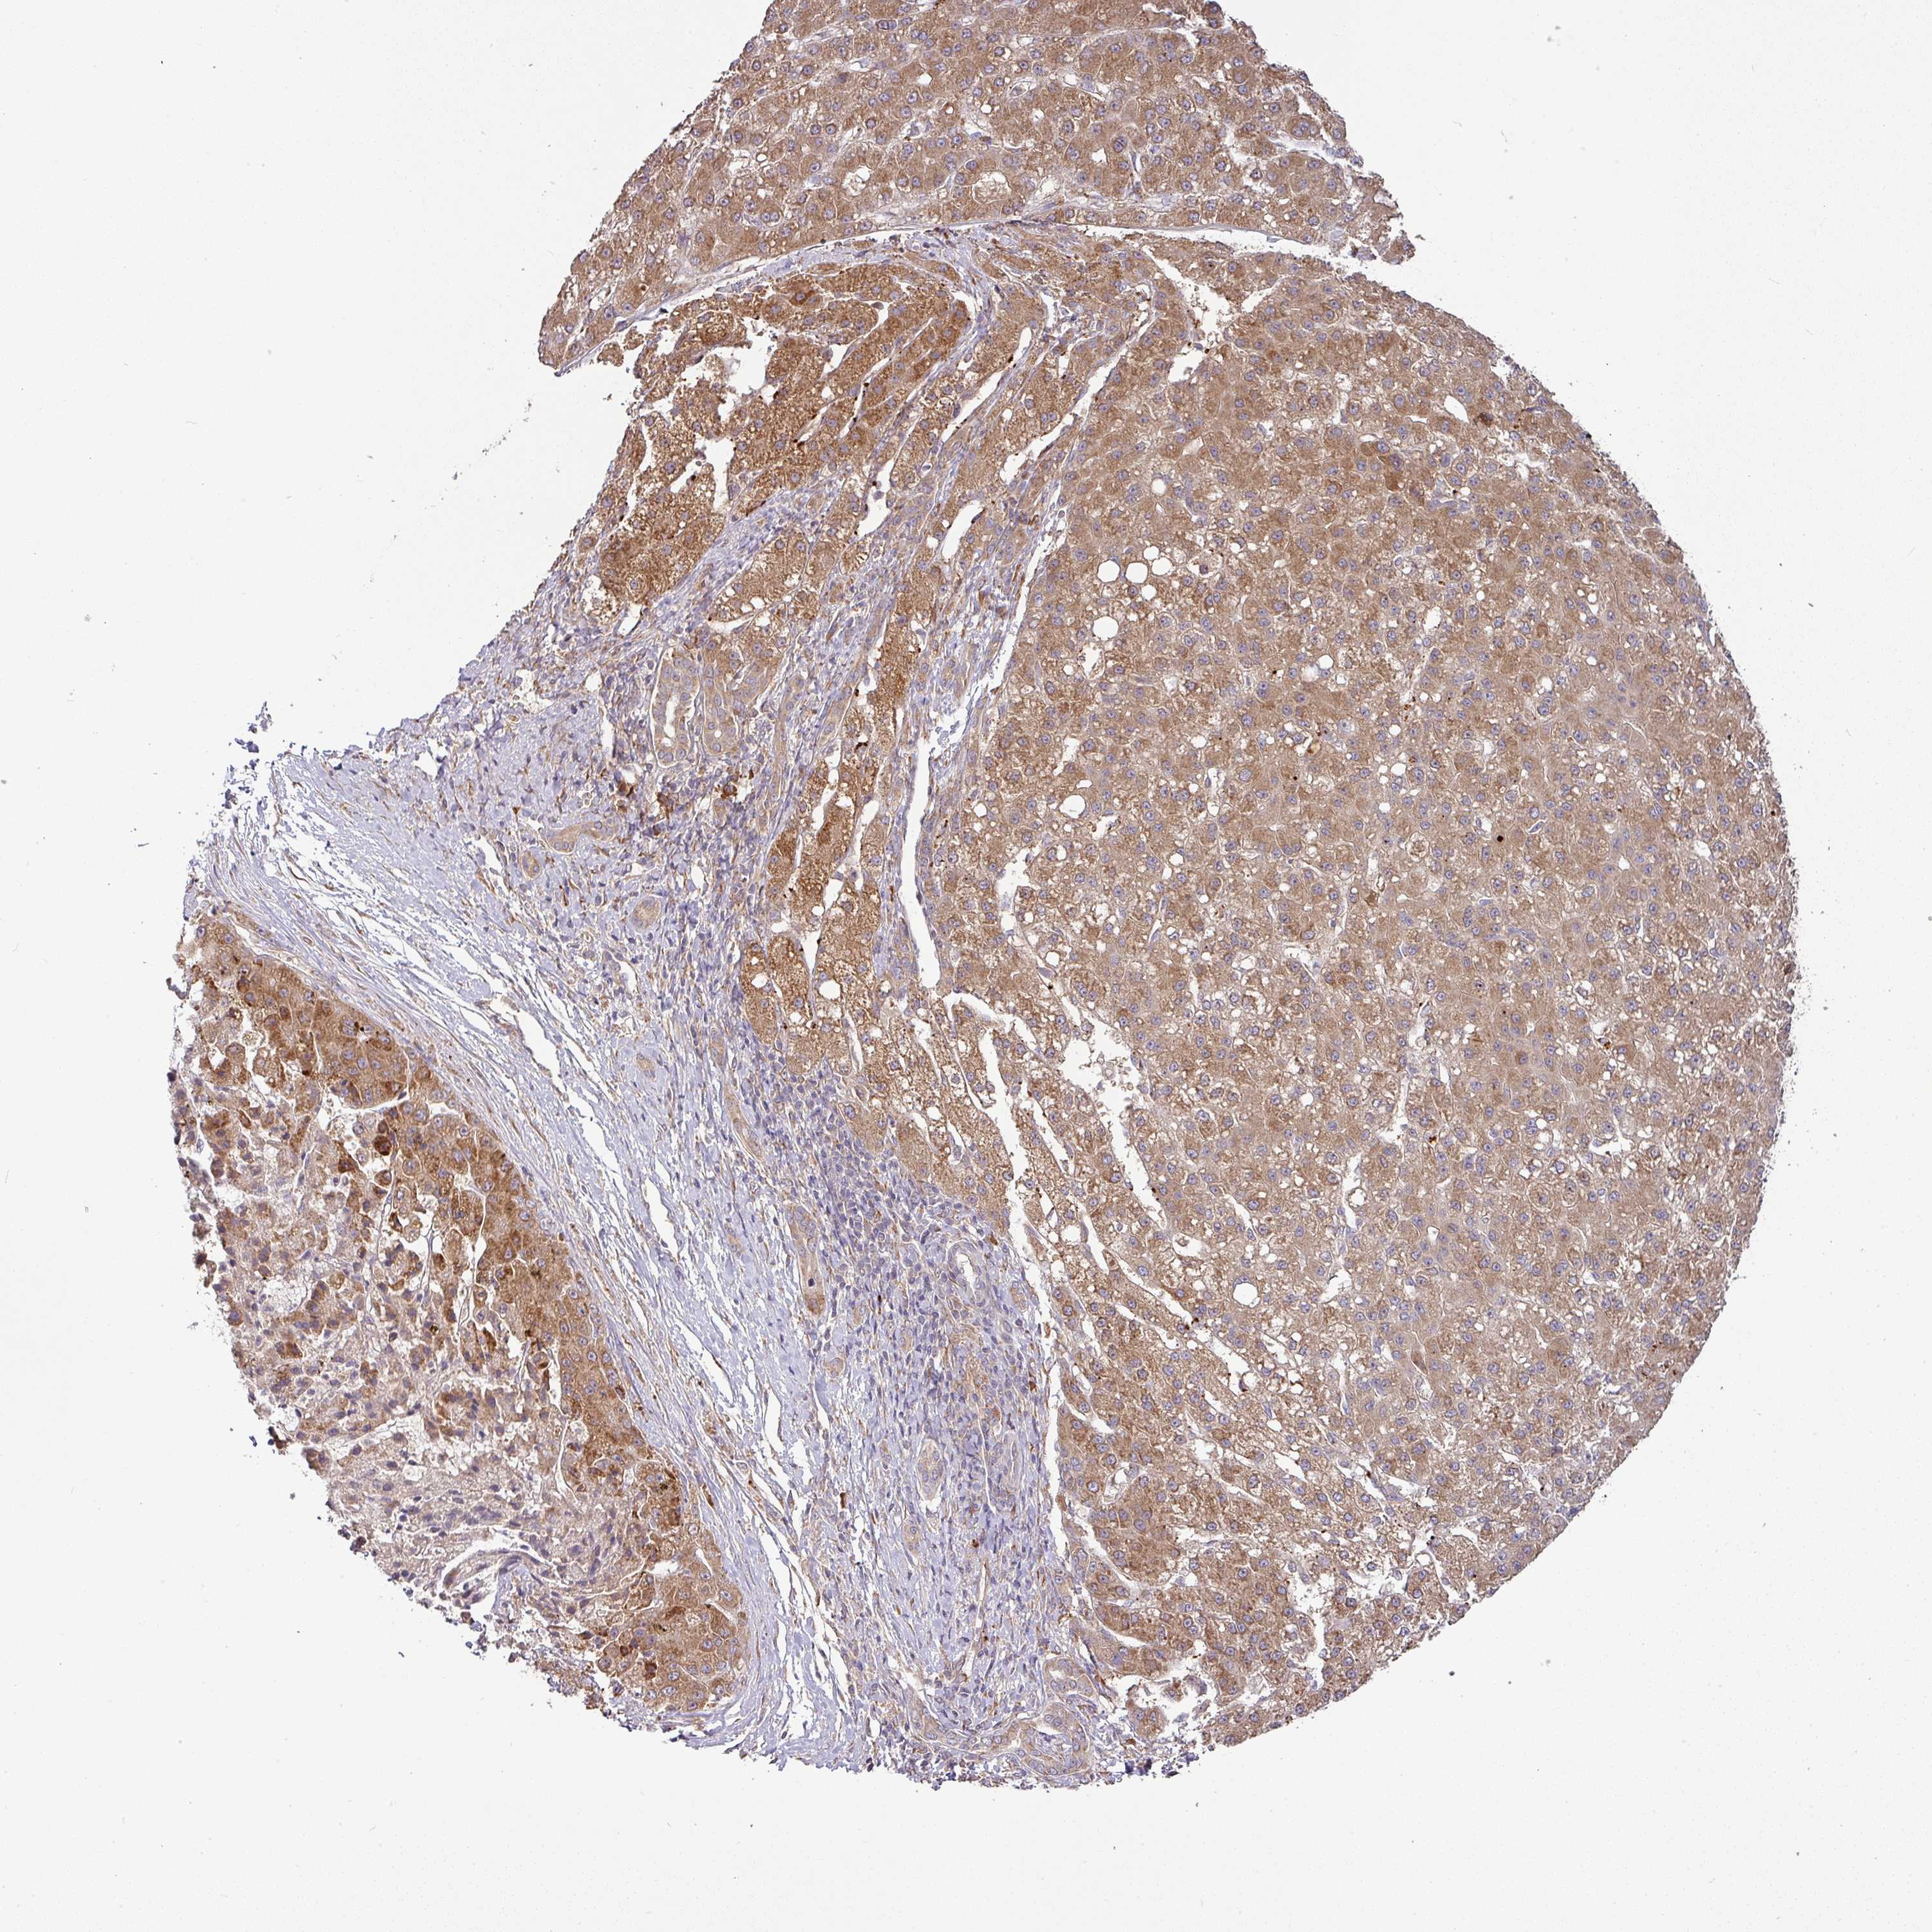

LIVER CANCER - Protein expressioni

A mouse-over function shows sample information and annotation data. Click on an image to view it in a full screen mode. Samples can be filtered based on level of antibody staining by selecting one or several of the following categories: high, medium, low and not detected. The assay and annotation is described here.

Note that samples used for immunohistochemistry by the Human Protein Atlas do not correspond to samples in the TCGA dataset.

Antibody stainingi

Antibody staining in the annotated cell types in the current human tissue is reported as not detected, low, medium, or high, based on conventional immunohistochemistry profiling in selected tissues. This score is based on the combination of the staining intensity and fraction of stained cells.

Each image is clickable and will lead to virtual microscopy that enables deeper exploration of all samples and also displays staining intensity scores, fraction scores and subcellular localization as well as patient and tissue information for each sample.

Antibody HPA053938

Staining

High

Medium

Low

Not detected

Intensity

Strong

Moderate

Weak

Negative

Quantity

>75%

75%-25%

<25%

None

Location

Nuclear

Cytoplasmic/membranous

Cytoplasmic/membranous,nuclear

Carcinoma, Hepatocellular, NOS

Cholangiocarcinoma